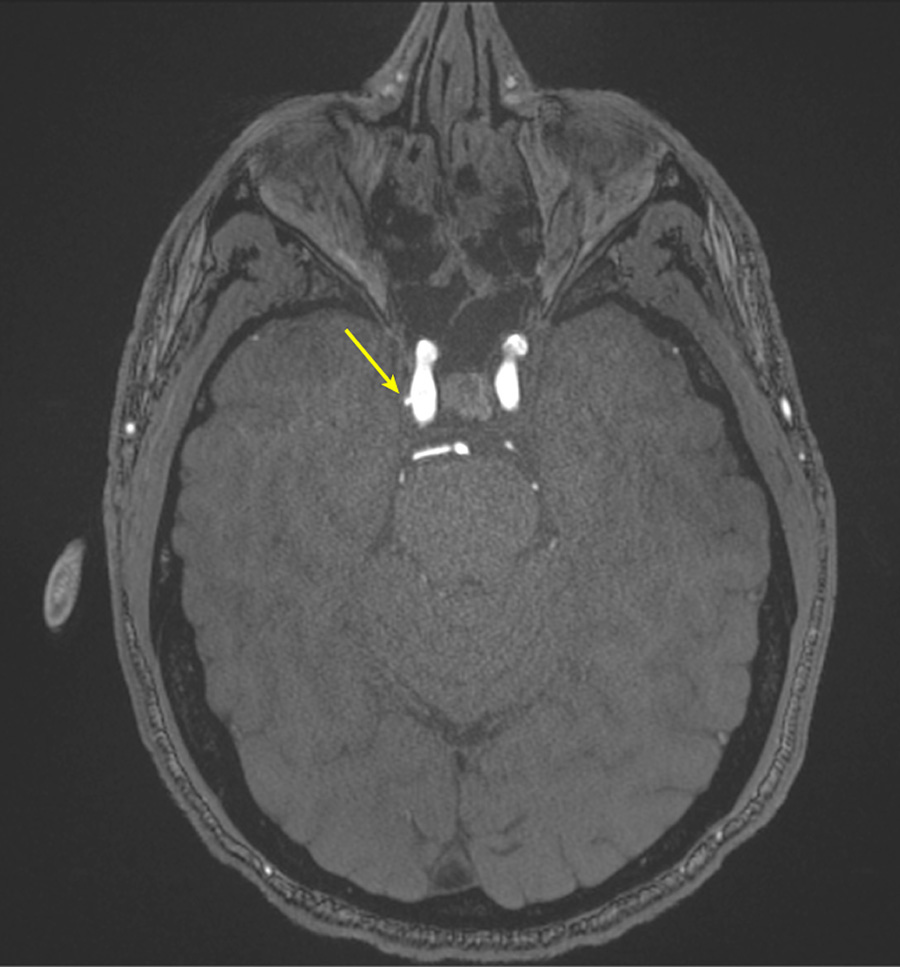

Figure 3. Representative axial time-of-flight MR angiography image in a 39-year-old male participant shows a laterally projecting intracranial aneurysm (arrow) originating from the right cavernous segment of the internal carotid artery.